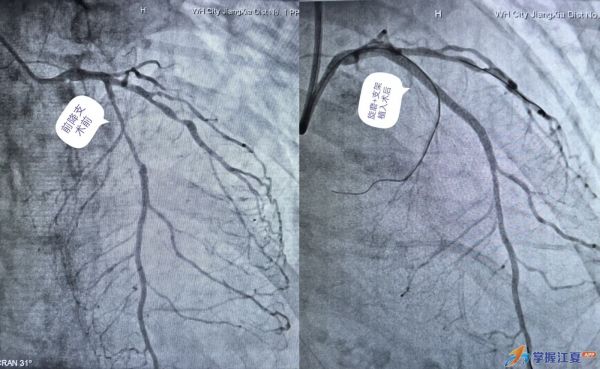

16日9时,林奶奶被推进介入诊疗中心,在多学科团队密切配合下行冠脉造影,结果显示为急性非ST段抬高型心肌梗死,且冠状动脉造影显示其右冠慢性闭塞、回旋支慢性闭塞、前降支重度狭窄并伴有严重钙化。同时,冠状动脉血管内超声示冠脉左主干至前降支中段血管内纤维增生混合重度钙化斑块,钙化呈360度环形钙化,证实了团队之前的预判,立即启动“冠状动脉旋磨术”处理钙化病变。

“既要有效磨除钙化,又必须保护正常的血管壁,就像在钢丝上跳舞,容不得半点差错。”在心血管内科团队的精密配合下,一根直径仅1.5毫米、细如发丝的旋磨导管被精准送至钙化最严重的血管段,以每分钟高达18万转的转速,对坚硬如石的钙化斑块进行高速、可控的精细化研磨,将其分解为比血细胞更小的微粒,经人体自然循环代谢清除。这一过程要求术者具备极高的手感与经验,精准控制力度与转速。经过紧张而细致的操作,团队成功“啃”下了钙化硬块,为后续支架的顺利植入开辟了平整、安全的通道。旋磨成功后,团队顺势完成球囊扩张与药物支架植入,术后造影显示原本严重狭窄的血管恢复畅通,血流显著改善。